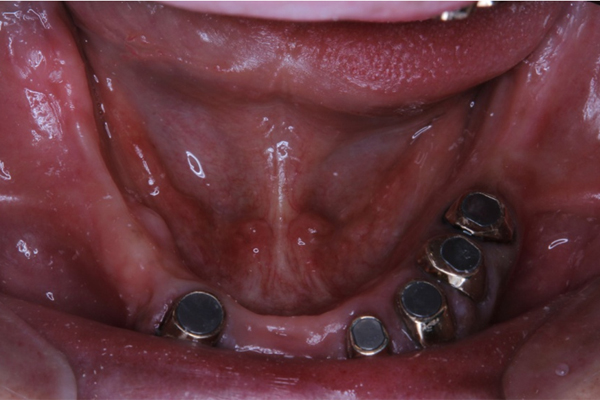

入れ歯を支える土台を埋め込みます。

インプラントが入った状態

下の義歯は2本、上の義歯には4本必要になります。